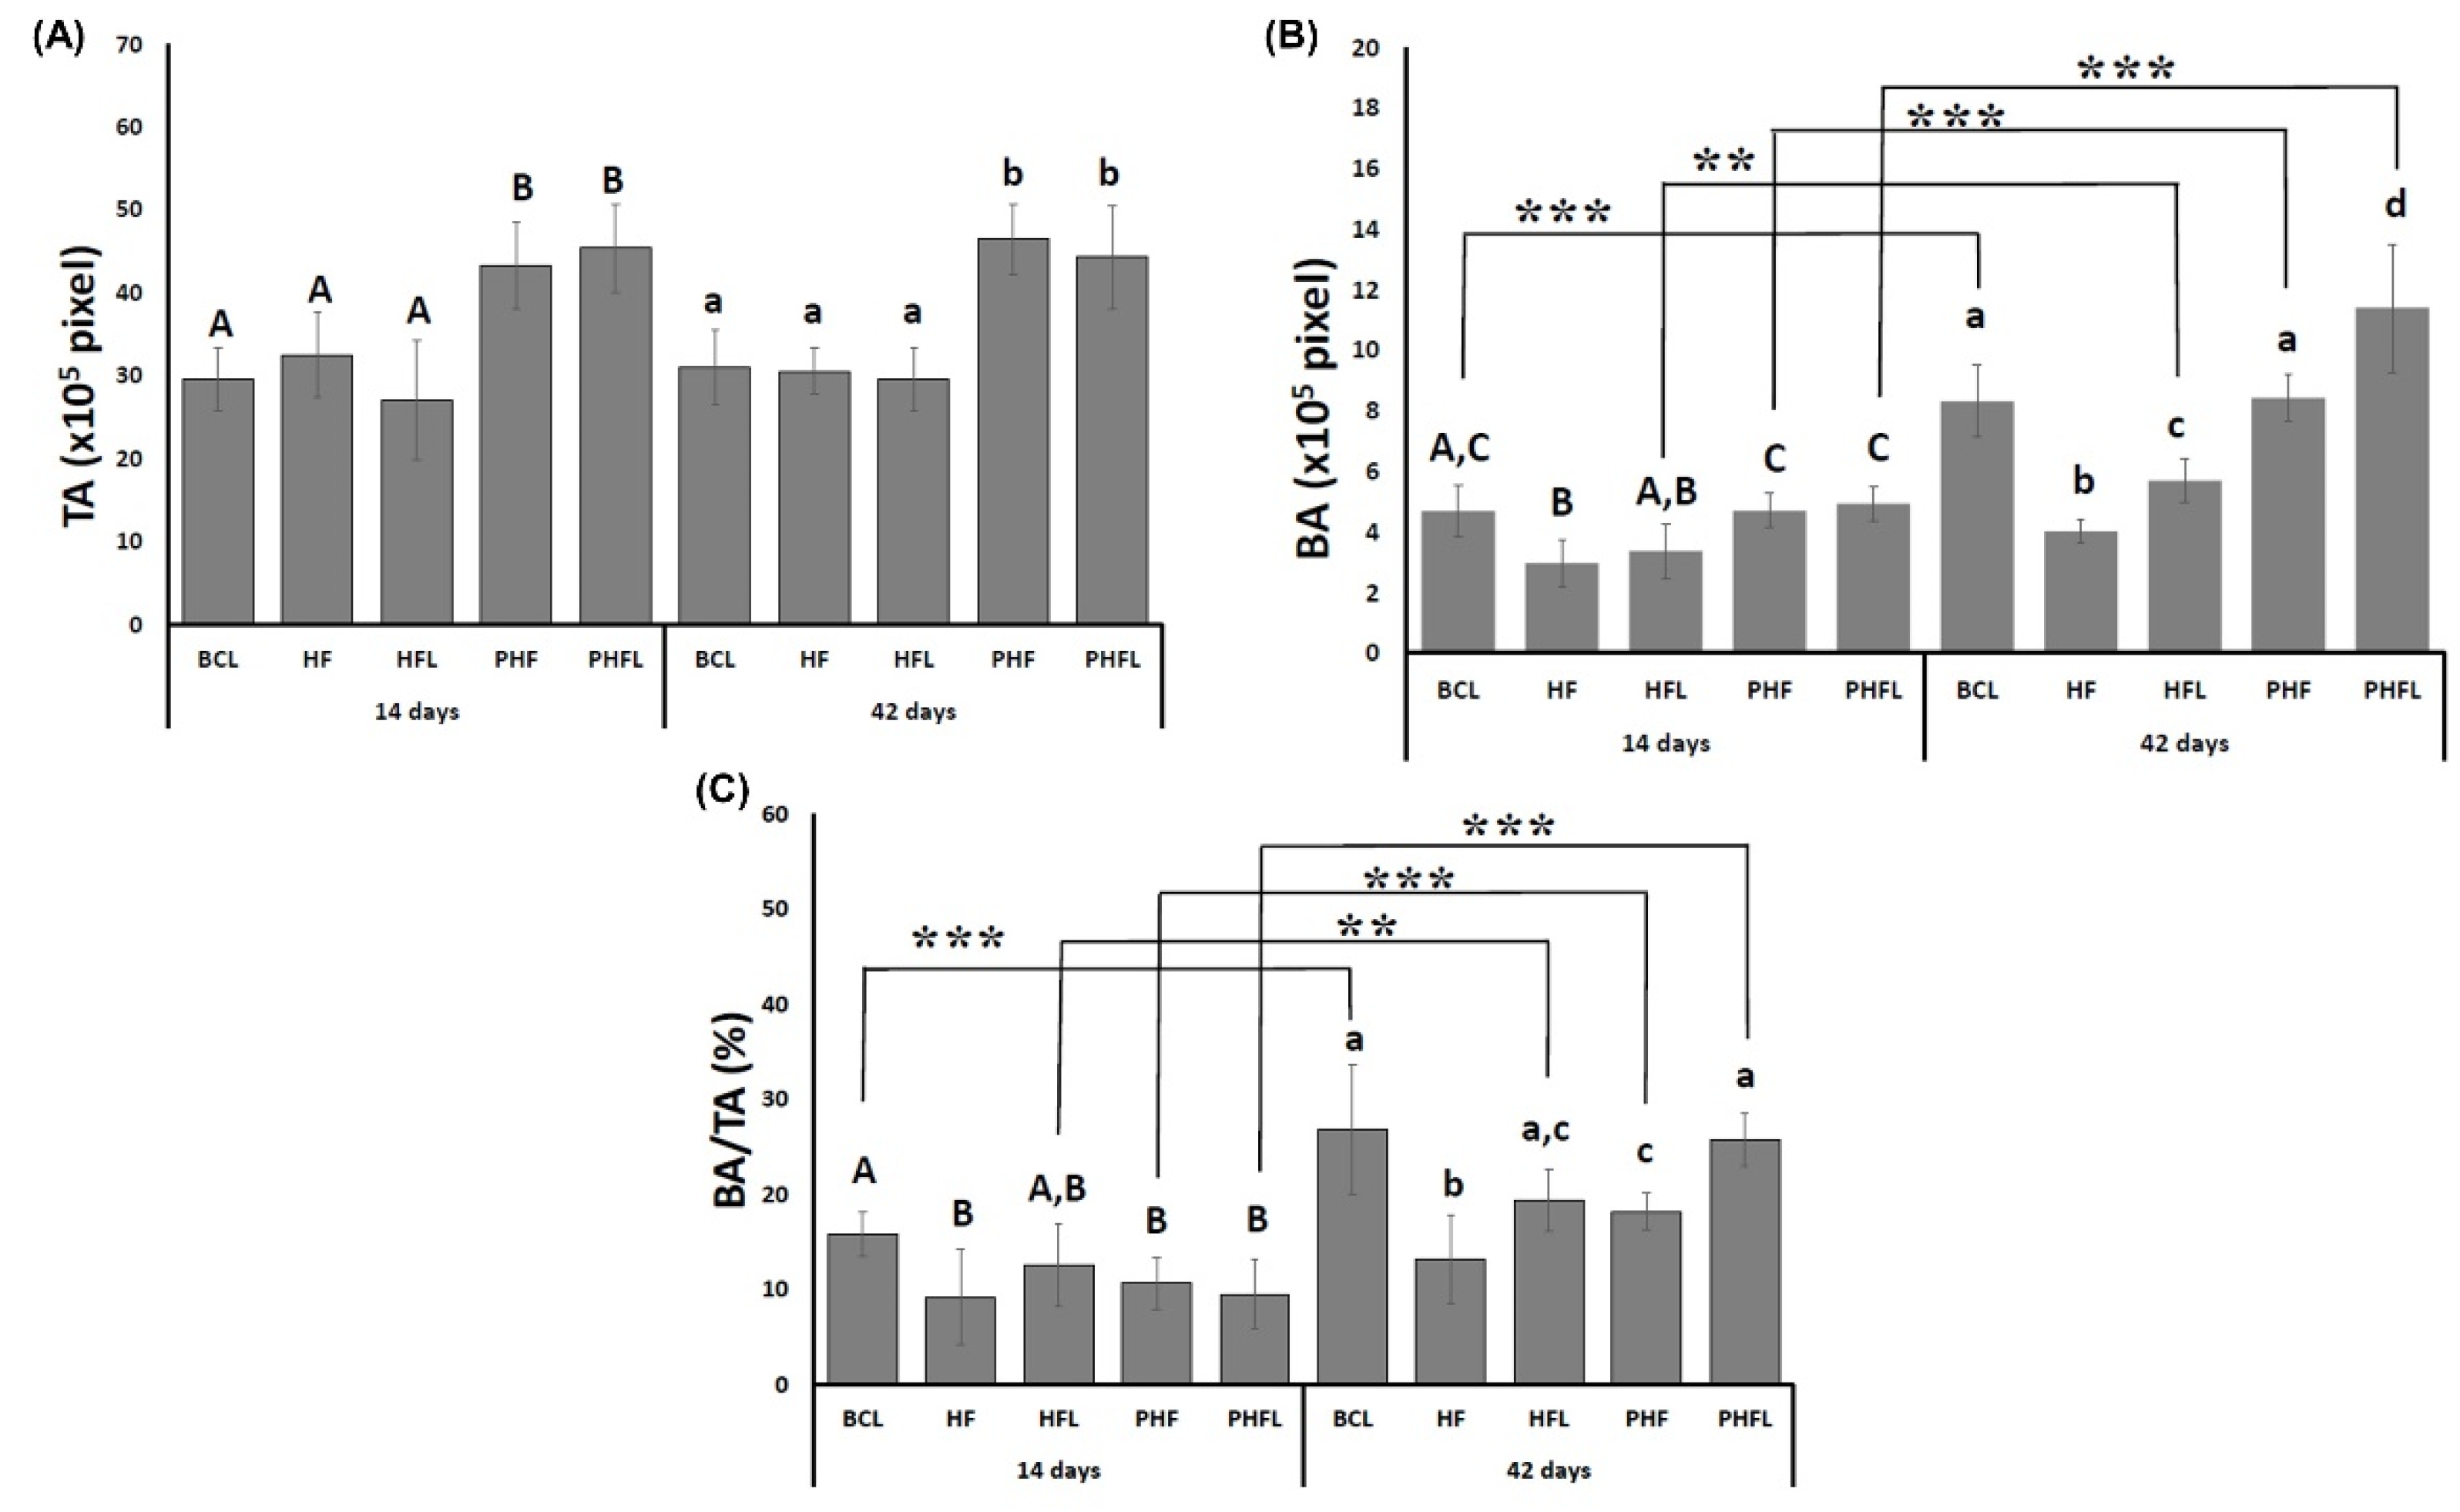

2.1. X-ray Computed Microtomography (µ-CT)

2.2. Histomorphological Analysis

2.3. Birefringence Analysis of Collagen Fibers in Bone Neoformation

4.9. Histomorphometric Analysis of HE-Stained Defects

4.10. Birefringence Analysis of Collagen Content of Bone Defects

4.11. Statistical Analysis